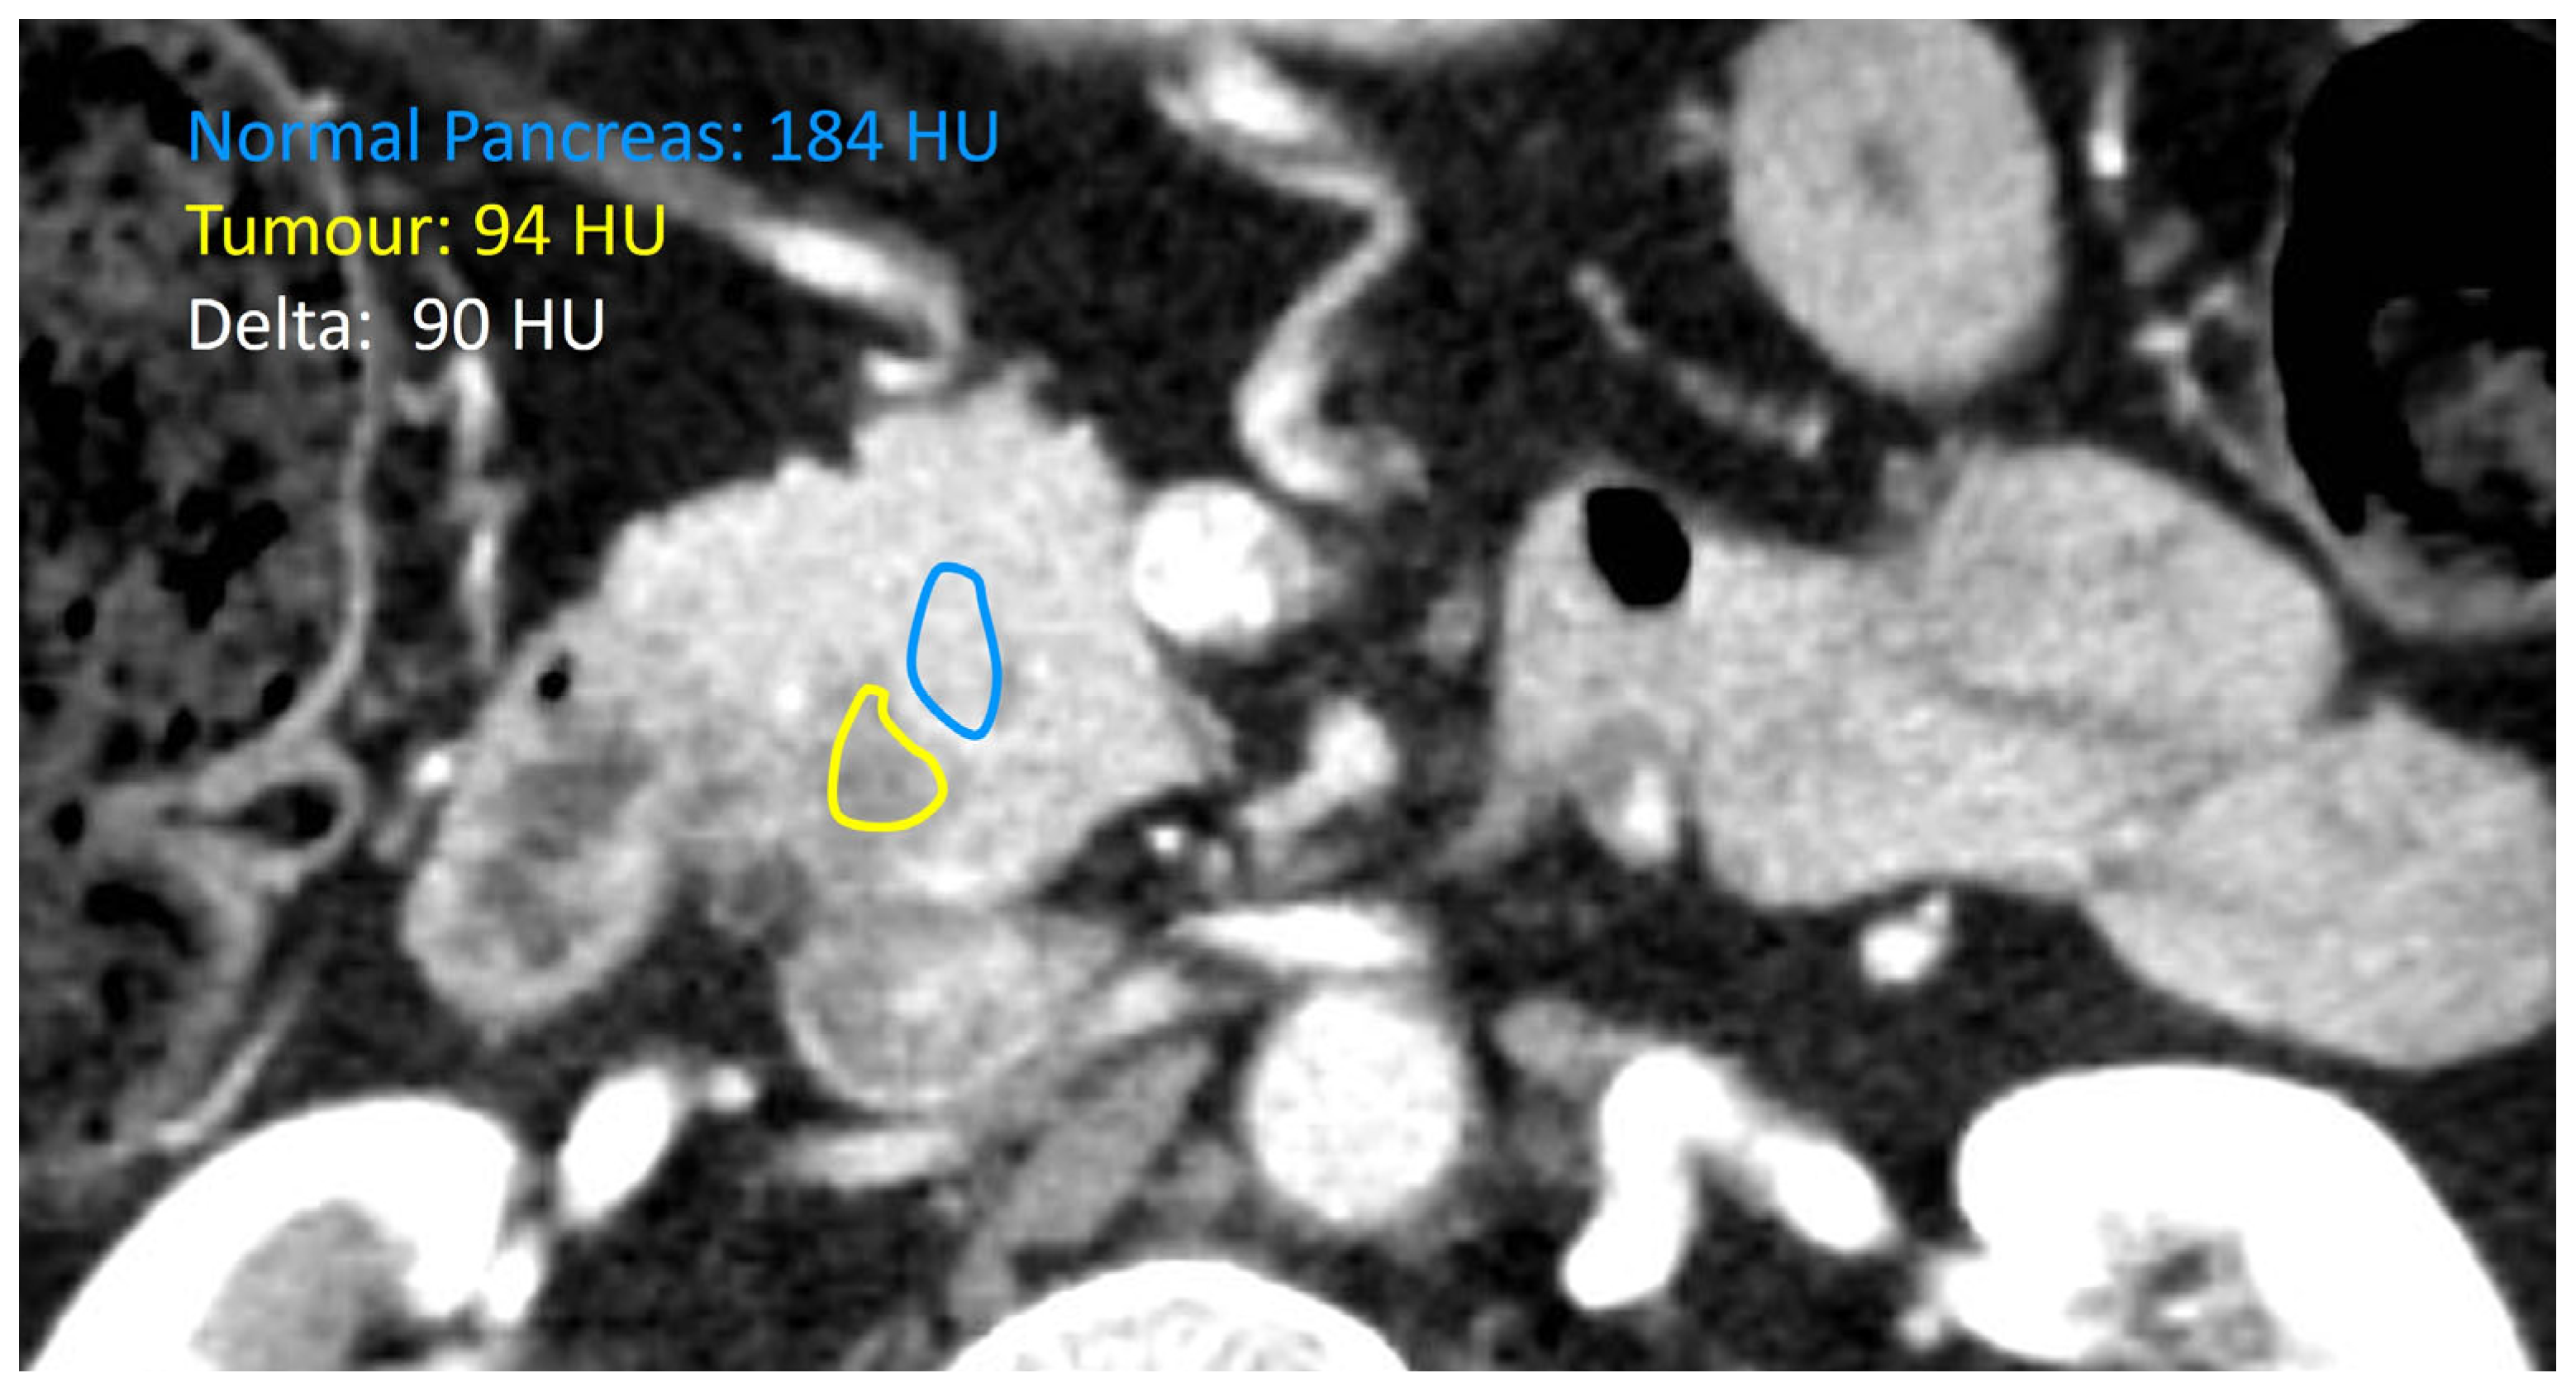

Preoperative multiphase CT (and MRI when available) was independently reviewed by a fellowship-trained abdominal radiologist, blinded to the outcomes. The attenuation difference between tumour parenchyma and surrounding stroma (deltaHU) was calculated on preoperative cross-sectional scans and categorized as either low (<26.5 HU) or high (>26.5 HU) based on ROC-derived Youden cutoffs. Figure 2 shows a representative slice from one of the study participants with the assigned deltaHU.

Figure 2.

Representative CT slice for one of our biophysical subtype analyses of pancreatic ductal adenocarcinoma showing the interface between tumour and normal pancreatic parenchyma, with the resulting deltaHU (Hounsfield Unit).